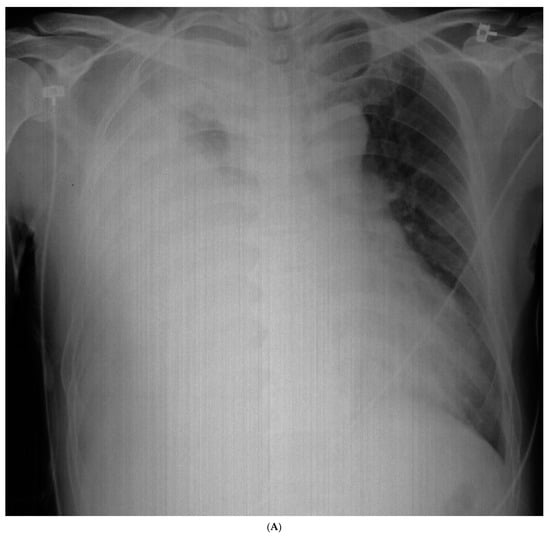

The chest radiography showed a massive right-sided pleural effusion (Figure 1A). Percutaneous catheter drainage was performed for the right-sided pleural effusion. The chest computed tomography showed a 3.3 cm × 3.0 cm mass in the right upper lobe (Figure 1B). The positron emission tomography/computed tomography revealed metastases in the left-sided supraclavicular lymph nodes, multiple bilateral mediastinal lymph nodes, and left scapula (Figure 2). The magnetic resonance imaging of the brain revealed multiple tiny cerebral and right cerebellar metastases (Figure 3). A percutaneous needle biopsy confirmed the diagnosis of lung adenocarcinoma (pT2aN3M1c, stage IVB); the analysis of the right-sided pleural effusion revealed metastatic adenocarcinoma. The genetic analysis revealed an exon 19 deletion in the EGFR gene. The laboratory tests, including the blood cell counts and chemistry, were within the normal ranges prior to treatment initiation. The patient was administered the EGFR-TKI afatinib (40 mg/day) as a first-line chemotherapy.

Figure 1.

Initial chest radiography and post-drainage chest computed tomography showing a right-sided pleural effusion. (A) Chest radiography revealed a massive right-sided pleural effusion. (B) After drainage of the right-sided pleural effusion, chest computed tomography showed a 3.3 cm × 3.0 cm mass in the right upper lobe.